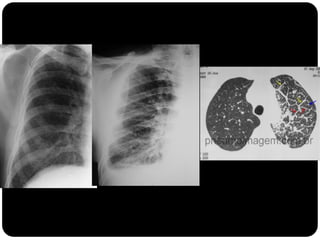

Diminuição da opacidade pulmonar-

cistos

1.Linfangioleiomi

omatose

2.PIL

3. Histiocistose de

langerhans

Bolhas de enfisema avançado